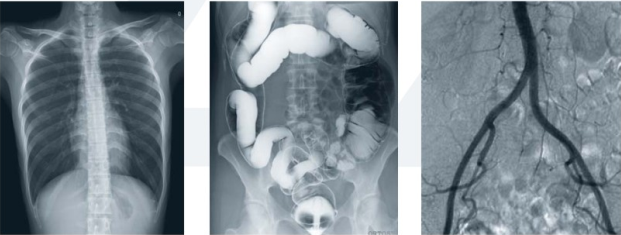

去醫(yī)院看病,經(jīng)常遇到這樣的困惑:DR、CT、MRI這些長相差不多的醫(yī)學影像設備有什么區(qū)別嗎?為什么有的時候用CT,有的時候用MRI,甚至有的時候做了DR還需做CT、MRI,是亂開檢查嗎?還是病情加重了?其實,它們的工作原理不同,各有分工,優(yōu)勢各異。以下小編帶你一一解讀。

DR(Digital Radiography)是數(shù)字化的拍片機器。采用非晶硅平板探測器把穿透人體的X線信息轉化為數(shù)字信號,通過計算機重新構建成圖像并進行一系列的處理。DR系統(tǒng)也是各大醫(yī)院的必備“武器”之一。常用于人體胸部及骨骼攝片,也可拍攝其他部位比如腹部、牙齒、頭顱等。

DR

3.對骨結構、關節(jié)軟骨及軟組織的顯示優(yōu)于傳統(tǒng)的X線成像,還可進行礦物鹽含量的定量分析;易于顯示縱隔結構如血管和氣管;對結節(jié)性病變的檢出率高于傳統(tǒng)的X線成像;在觀察腸管積氣、氣腹和結石等含鈣病變優(yōu)于傳統(tǒng)X線圖像;體層成像優(yōu)于X線體層攝影;胃腸雙對比造影在顯示胃小區(qū)、微小病變和腸粘膜皺襞上,數(shù)字化圖像優(yōu)于傳統(tǒng)的X線造影。

CT:

CT(Computed Tomography)即電子計算機體層掃描。用X射線束對人體某部一定厚度的層面進行掃描,由探測器接收透過該層面的X射線,轉變?yōu)榭梢姽夂?,由光電轉換變?yōu)殡娦盘枺俳?jīng)模擬/數(shù)字轉換器(analog/digital converter)轉為數(shù)字,輸入計算機處理。